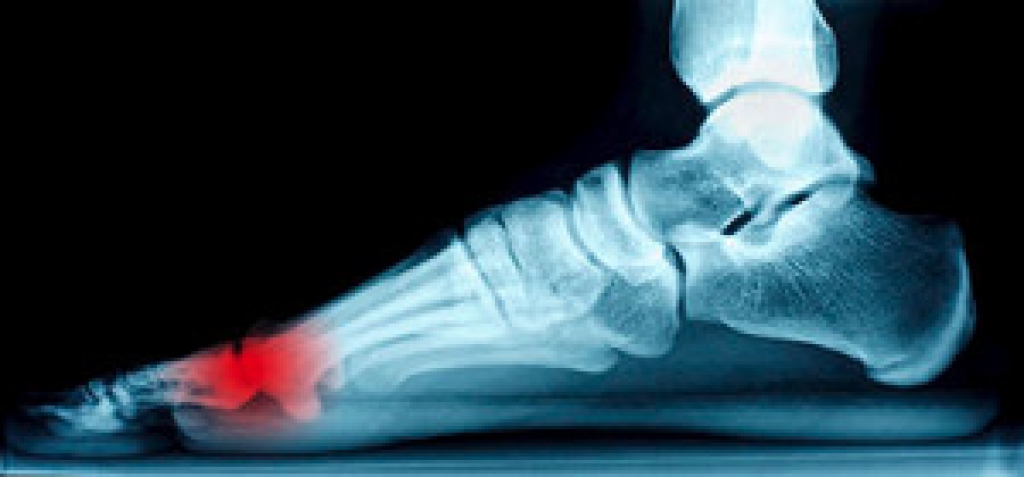

The Achilles tendon is the band of tissues that connects the back of the calf muscles to the heel bone. Common causes of pain primarily consist of ruptures and tendonitis. During a tear or rupture of the Achilles tendon, some of the fibers may remain connected (partial tear) or tear completely. Ruptures are likely to occur when there is a sudden increase in exercise and may be signaled by a popping or snapping sound, pain in the back of the legs, or swelling around the heel. Achilles tendonitis occurs when the tendon becomes inflamed, resulting in pain, stiffness, or swelling. Achilles tendonitis can occur from excessive strain, tight calf muscles, or not warming up before exercising. If you are experiencing pain in your Achilles tendon it is recommended to have it checked by a podiatrist for a proper diagnosis.

The Achilles tendon is a tendon that connects the lower leg muscles and calf to the heel of the foot. It is the strongest tendon in the human body and is essential for making movement possible. Because this tendon is such an integral part of the body, any injuries to it can create immense difficulties and should immediately be presented to a doctor.

There are various types of injuries that can affect the Achilles tendon. The two most common injuries are Achilles tendinitis and ruptures of the tendon.